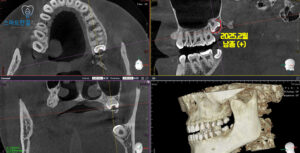

화서동치과 화서동치과

2025.2월 / 2026.3월

<CT 촬영 후 비교 진단>

CT를 촬영하여 확인해 보니,

일 년전과 비교하여

낭종이 확실히 커진 모습을 볼 수 있었어요.

이러한 낭종은 초기에는

별다른 증상이 없는 경우가 많지만,

시간이 지나면서 점차 크기가 커질 경우

주변 치조골을 약화시키거나

인접 치아의 치근 흡수,

상악동과의 연관 문제 등을 유발할 수 있는데요.

그래서 화서동치과 스마트한결에서는

매복된 사랑니 발치와 함께

낭종 적출술을 동시에 시행하는 방향으로

치료 계획을 수립하였답니다.(^^)